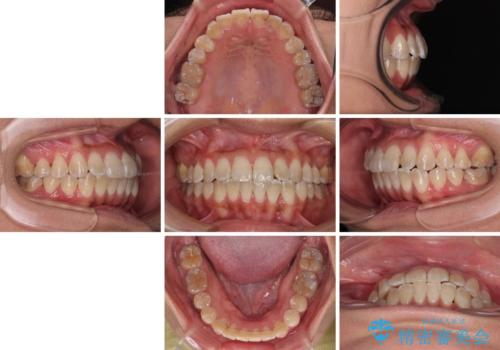

- 上下の前歯のでこぼこを気にして来院された患者様です。

職場の都合により、表側のワイヤー装置や着脱作業が頻繁なマウスピース矯正は困難とのことで、全く目立たない裏側矯正装置を用いて口元を整えることとしました。

途中転勤や出産があり、通院できない期間が長くありましたが、無事に歯列を整えることができました。